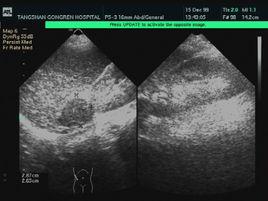

腫瘤組織在發展階段變異較大,故在X線檢查與無固定的特異性徵象。根據鈣化或骨化程度可顯示不同透明影或緻密影。腫瘤與周圍骨組織分界清晰、周邊有骨質硬化。無骨膜反應。

(一)中心型為常見型,典型表現為邊緣清晰的囊狀骨質破壞區,皮質膨脹變薄。如皮質破裂,形成軟組織腫塊。腫瘤內有不同程度的成骨或鈣化陰影,至斑點或索狀。少數呈單囊形破壞而無鈣化影。如為多囊性,則有散在病灶。腫瘤附近骨質輕度增生硬化。一般無骨膜反應。